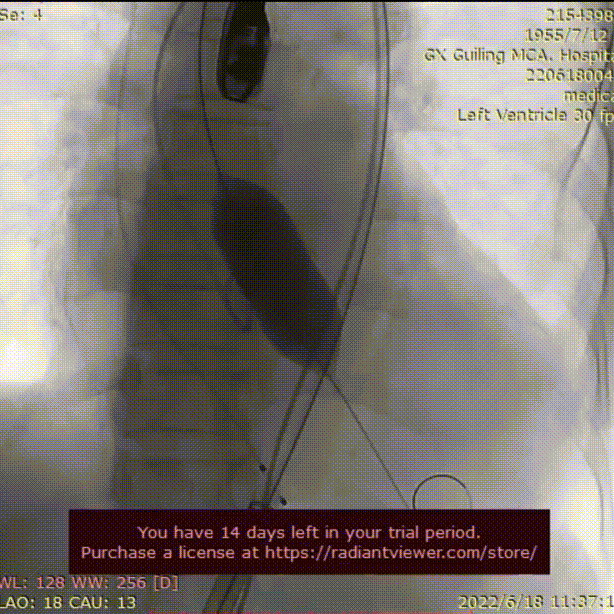

主动脉根部造影

23mm球囊预扩

AV29瓣膜定位

AV29瓣膜释放到工作位

AV29瓣膜回收调整后定位

AV29瓣膜再次释放到工作位

AV29瓣膜释放后造影,形态良好

术后血管造影,无血管损伤